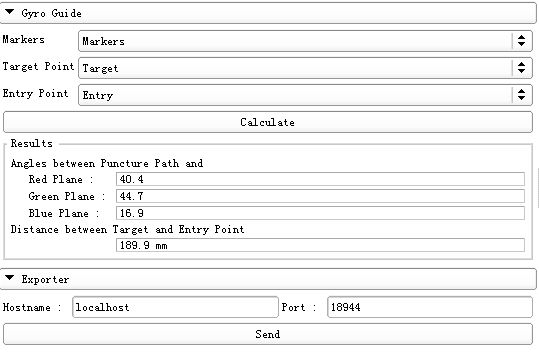

- The module should be used in cooperation with “Markups” module. First, it is required to choose five fiducial points to define two mutually-perpendicular planes as the Registration Markers. Second, set a target point and an entry point. Third, click the “Calculate” button to obtain the puncture path information, including the puncture depth and the angles between the puncture path and the reference planes. Finally, these results are displayed on a monitor or transmitted to the gyroscope-based device to assist the surgical operation.

- 1 Select the fiducial list - Markers as the markers which define the reference planes.

- 2 Select the fiducial list – Target as the target point

- 3 Select the fiducial list – Entry as the entry point

- 4 Calculate puncture path information

- Click the “Calculate” button. The puncture path information will be displayed in the “Results” section.

- 5 Export the results

- Input IP address and port of the puncture instrument in the “Exporter” panel. Click “Send”. The calculated puncture path information could be transmitted to the gyroscope-based device to facilitate the surgical operation.